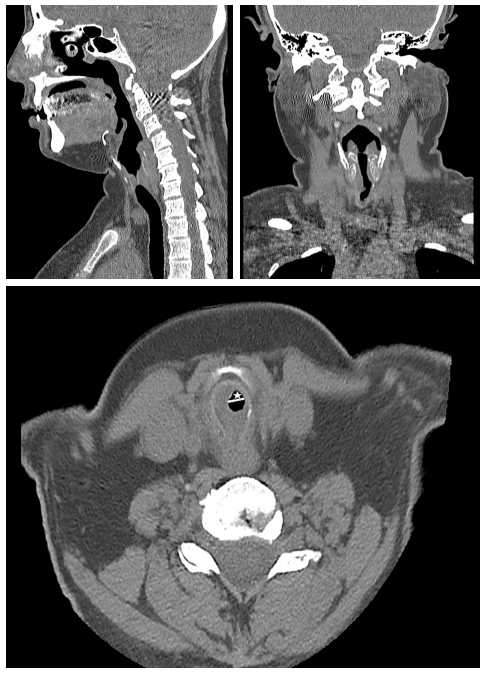

A 37-year-old female patient presented with symptoms of eye swelling, redness, protrusion, and shortness of breath. During examination, she had biphasic stridor, no edema in the nasal mucosa, and no saddle nose deformity. Elevated acute phase reactants and normocytic anemia were observed. Urine microscopy findings were normal, proteinuria was not detected, and immunological tests showed positive p-ANCA (perinuclear antineutrophil cytoplasmic antibody). Thorax computed tomography (CT) revealed stenosis below the cricoid cartilage and millimetrically small lymph nodes at this level, while no pathology was observed in the lung parenchyma. The biopsy results indicate the presence of inflammatory infiltration and edema in the submucosal layer, where a significant number of lymphocytes and neutrophils were observed. However, there was no evidence of granulomatous reaction. The patient was diagnosed with limited granulomatosis with polyangiitis (GPA), formerly called Wegener’s granulomatosis, based on clinical and laboratory findings and was treated with methylprednisolone and azathioprine. When dyspnea complaints increased, rituximab was started. The control neck CT revealed progression of stenosis in the subglottic region and increased concentric wall thickness, with the narrowest air column measured at 6 mm (Figure 1). During rigid bronchoscopy, the patient experienced respiratory arrest and required an emergency tracheostomy. A written informed consent was obtained from the patient.